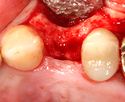

An incision is made across the area and the flap of gingiva is opened to show the bone of the jaw.

An incision is made across the gingiva, and the flap of tissue is reflected to show the bone of the jaw.

A healing abutment is attached to the implant fixture and the gingiva flap is sutured around the healing abutment.

A healing abutment is attached to the implant fixture, and the flap of gingiva is sutured around the healing abutment.